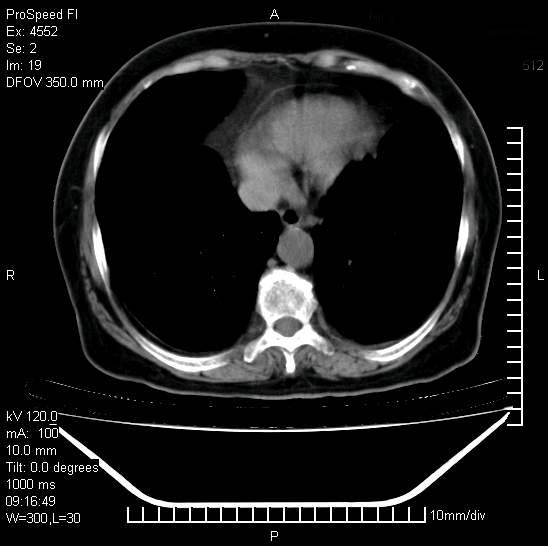

今天ct

十几年前曾患肺结核,一周前突咳血约100ml,中性粒细胞稍高,诊断两上肺陈旧结核,下肺炎症,给予抗炎治疗,近几日晚上高热,39度,仍咳少量血,4天前ct及今天ct上传。